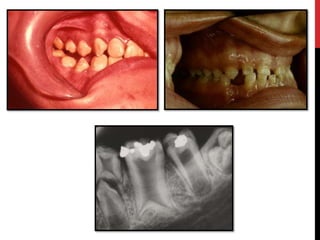

• #28 Hypoplastic amelogenesis imperfecta: Basic alteration centers on inadequate deposition of enamel matrix. Generalized pattern: Pin point to pin head sized pits are scattered across the surface of the teeth. The buccal surface of the teeth are affected more severely and the pits are arranged in rows or columns. Staining of the pits may occur. The enamel between pits is of normal thickness, hardness and coloration.

• #30 Localized pattern The affected teeth demonstrates horizontal rows of pits,a linear depression,or one large area of hypoplastic enamel surrounded by a zone of hypocalcification. Altered area is located in the middle third of the buccal surfaces of the teeth.The incisial third or occlusal surfaces is not affected. Both the dentitions are affected.The autosomal recessive type is more severe and typically demonstrates involvement of all teeth in both the dentitions.

• #31 Autosomal dominant smooth pattern: The enamel of all teeth exhibits a smooth surface and is thin hard and glossy. The absence of appropriate enamel thickness results in teeth that are shaped like crown preparations and demonstrate open contact points. The color of teeth varies from opaque white to translucent brown. Radiographically the teeth exhibit a thin peripheral outline of radiopaque enamel.

• #32 X-linked smooth pattern Exhibits diffuse thin, smooth, and shiny enamel in both dentitions. The teeth often have the shape of crown preparations,and the contacts points open. The color varies from brown to yellow-brown. Radiographs show a peripheral outline of radioopaque enamel.unerupted teeth undergo resorption. An open bite is seen in almost all males and in a minority of females. X-linked rough pattern The enamel is thin, hard and rough surfaced.As in smooth forms, the teeth taper towards the incisial occlusal surface and demonstrate open contact points. The color varies from white to yellow white. The enamel is denser than that seen in smooth patterns and the teeth are less vulnerable to attrition. Radiographs exhibit a thin peripheral outline of radio dense enamel.

• #33 The enamel is softer than normal and tends to chip of from the underlying dentin. Radiographically the affected enamel exhibits a radiodensity that is similar to dentin.

• #34 Pigmented pattern The surface enamel is mottled and agar brown. The enamel often fractures from the underlying dentin. Anterior open bite and unerupted teeth exhibiting resorption are common.

• #35 X linked pattern The affected males exhibits different patterns in the deciduous and permanent dentitions. The deciduous teeth are opaque white with a translucent mottling, the permanent teeth are opaque yellow white and may darken with age.

• #37 Snow capped patterns Exhibit a zone of white opaque enamel on the incisal or occlusal one third of the crown. The affected teeth often demonstrates an anterior to posterior distribution .Both the dentitions are affected.